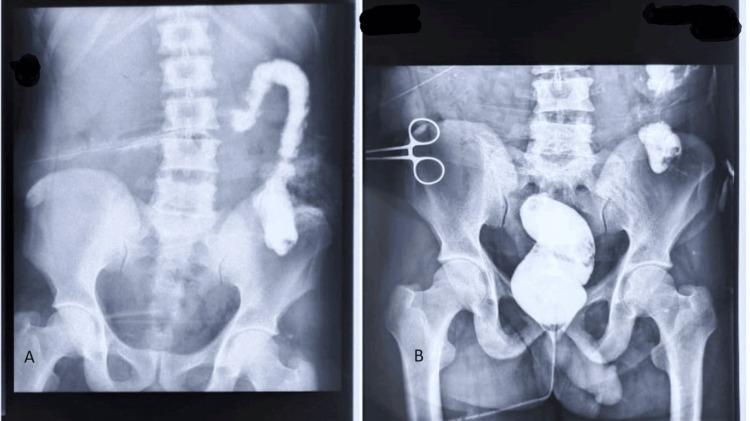

Compound volvulus or ileosigmoid knotting is an uncommon surgical emergency that causes intestinal obstruction. The sigmoid and ileum are mostly involved in this closed-loop intestinal obstruction. It is regarded as a rather uncommon cause of intestinal obstruction. It's important to distinguish between an ileosigmoid knot and a simple sigmoid volvulus since the management of the two is different. CT and MRI are more helpful in the diagnosis than abdominal X-ray findings, which are not pathognomonic. After resuscitation, a patient with ileosigmoid knotting typically needs an emergency laparotomy. Different resectional and non-resectional surgical procedures may be employed depending on the viability of the ileum and sigmoid colon.

复合性肠扭转或回乙状结肠扭结是一种导致肠梗阻的罕见外科急症。乙状结肠和回肠最常受累于这种闭袢性肠梗阻。它被视为肠梗阻的一种相当罕见的病因。区分回乙状结肠扭结和单纯乙状结肠扭转很重要,因为二者的处理方式不同。计算机断层扫描(CT)和磁共振成像(MRI)在诊断中比腹部X线检查结果更有帮助,腹部X线检查结果不具有特征性。复苏后,回乙状结肠扭结患者通常需要急诊剖腹手术。根据回肠和乙状结肠的活力,可能会采用不同的切除性和非切除性手术方法。